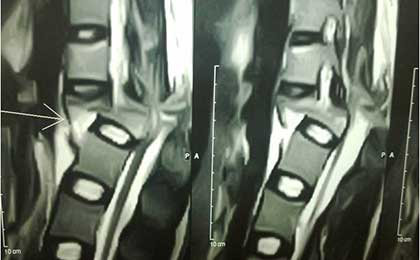

PRE OP MRI SPINE INJURY

PRE OP L5-S1 MRI